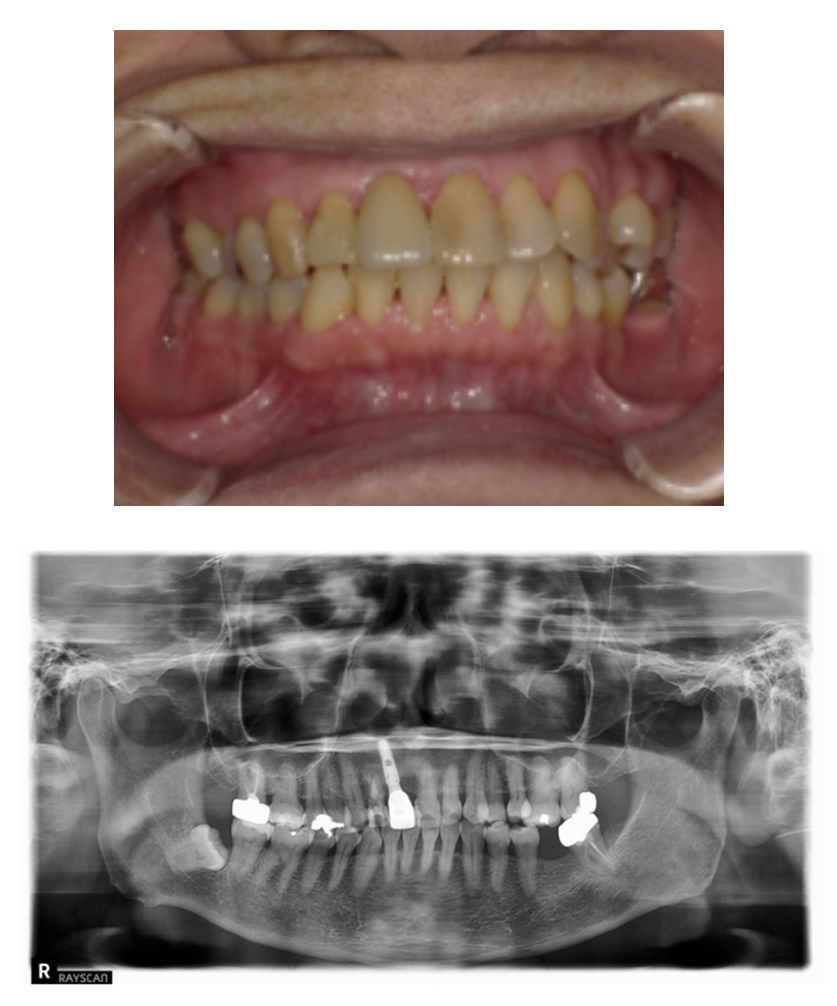

02 症例

歯の根の状態が悪いためインプラントにしたい

Before

After

| 治療内容 | 前歯の見た目が悪く、歯の根の状態も悪いのでインプラントにしたい。 |

| 患者様 | 50代女性 |

| 主訴 | 歯の根の状態が悪いためインプラントにしたい |

| 治療期間(目安) | 5ヶ月 |

| 治療費(税込:目安) | ¥2,702,700 (土台:5本、被せ物:7本) |

| リスク | 術後に多少の痛みや腫れが出ることがある。歯肉退縮がおきると、歯と歯肉の間に隙間が生じることがあります。 |